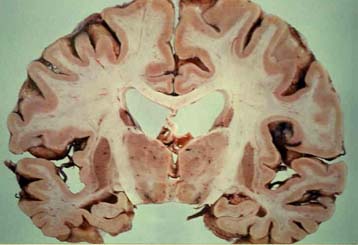

Σύμφωνα με δημοσίευση των ερευνητών στο περιοδικό Archives of General Psychiatry, ο όγκος της λευκής ουσίας αυξάνεται μέχρι την ηλικία των 44 ετών στους μετωπιαίους λοβούς του εγκεφάλου, και μέχρι τα 47 χρόνια στους βρεγματικούς λοβούς. Στη συνέχεια αρχίζει να εκφυλίζεται προοδευτικά, όπως συμβαίνει και με τη φαιά ουσία από την ηλικία των 20 περίπου ετών.

Η λευκή ουσία είναι το δίκτυο των νευρικών ινών που βρίσκεται κάτω από το εξωτερικό στρώμα της φαιάς ουσίας. Πρόκειται για νευρικούς άξονες που συνδέουν τους νευρώνες μεταξύ τους και επιτρέπουν την επικοινωνία μεταξύ διαφορετικών περιοχών του εγκεφάλου.

«Εάν ο εγκέφαλος παρομοιαστεί με το Διαδίκτυο, η φαιά ουσία είναι ένας υπολογιστής, και η λευκή είναι οι τηλεφωνικές γραμμές που συνδέουν τον υπολογιστή αυτόν με όλους τους υπόλοιπους» αναφέρει ο δρ. Τζορτζ Μπαρτζόκις, επικεφαλής της ερευνητικής ομάδας στην αμερικανική Υπηρεσία Υποθέσεων Βετεράνων.

Επιβεβαίωσε παλιότερες έρευνες που έδειχναν ότι η μάζα της φαιάς ουσίας μειώνεται γραμμικά σε σχέση με την ηλικία, αλλά παράλληλα διαπίστωσε ότι η λευκή ουσία αυξανόταν, τουλάχιστον στις περιοχές που εξετάστηκαν.

Το εύρημα αυτό είναι ιδιαίτερα σημαντικό, καθώς οι μετωπιαίοι και οι βρεγματικοί λοβοί (το πρόσθιο τμήμα του εγκεφάλου) είναι επιφορτισμένοι με ανώτερες νοητικές λειτουργίες και ελέγχουν εν μέρει τη μνήμη και βασικά στοιχεία της συμπεριφοράς.